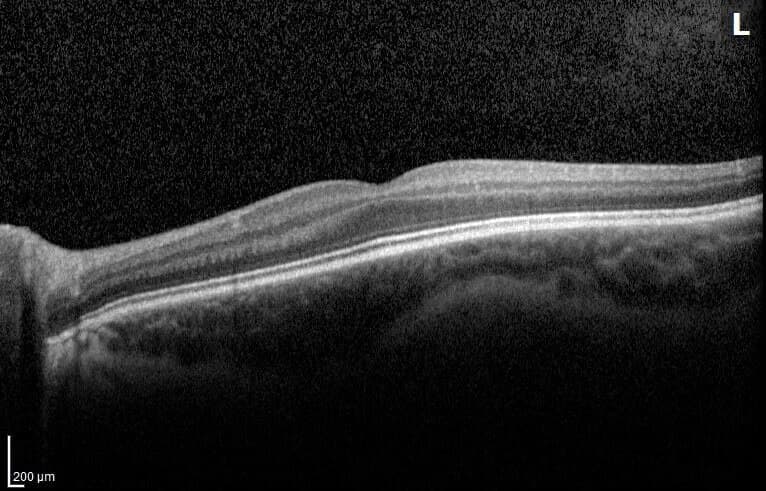

OCT

La OCT de mácula permite diagnosticar y seguir enfermedades de la región central de la retina. La OCT de nervio óptico ayuda en glaucoma y otras neuropatías.

Tomografía de coherencia óptica de mácula